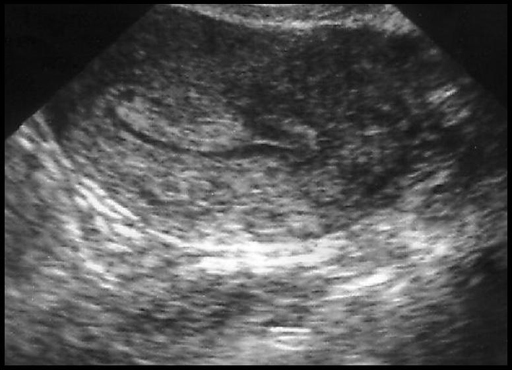

Polype muqueux